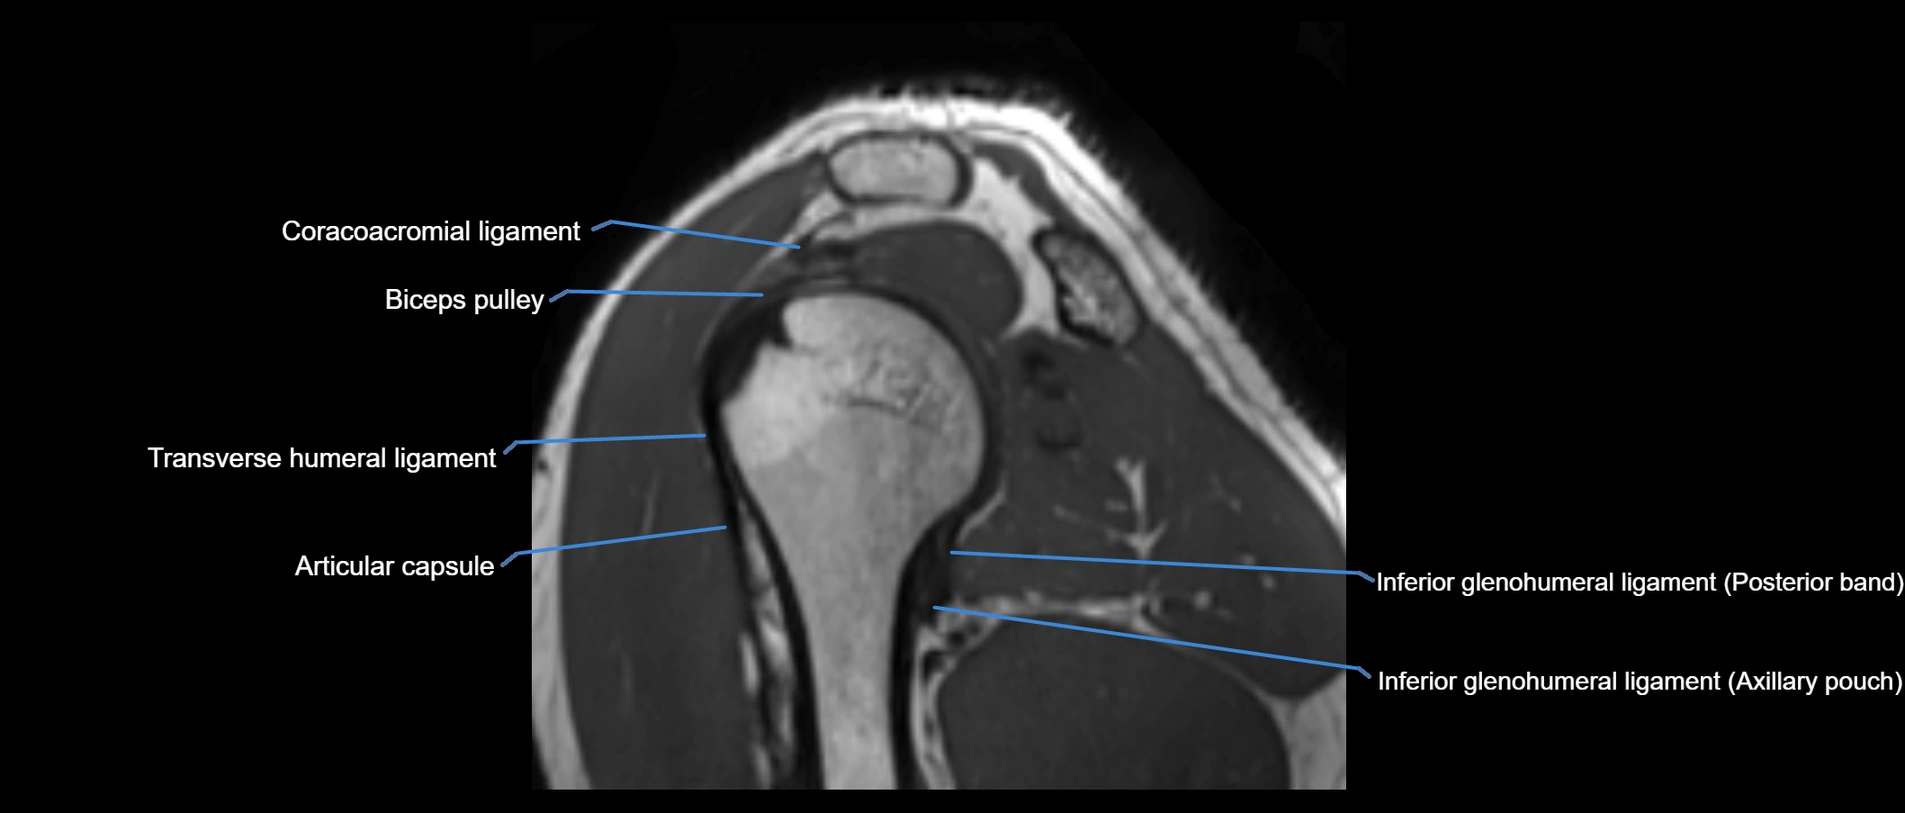

CT image

image

CT Appearance

Non-Contrast CT:

• Ligament: Not directly visualized due to small size and low density.

• Bony landmarks: Lateral clavicle and acromion clearly seen; cortical margins well defined.

• Pathology: Detects fractures, joint subluxation, osteophytes, and degenerative changes.

• Alignment assessment: Evaluates AC joint spacing and clavicular displacement.